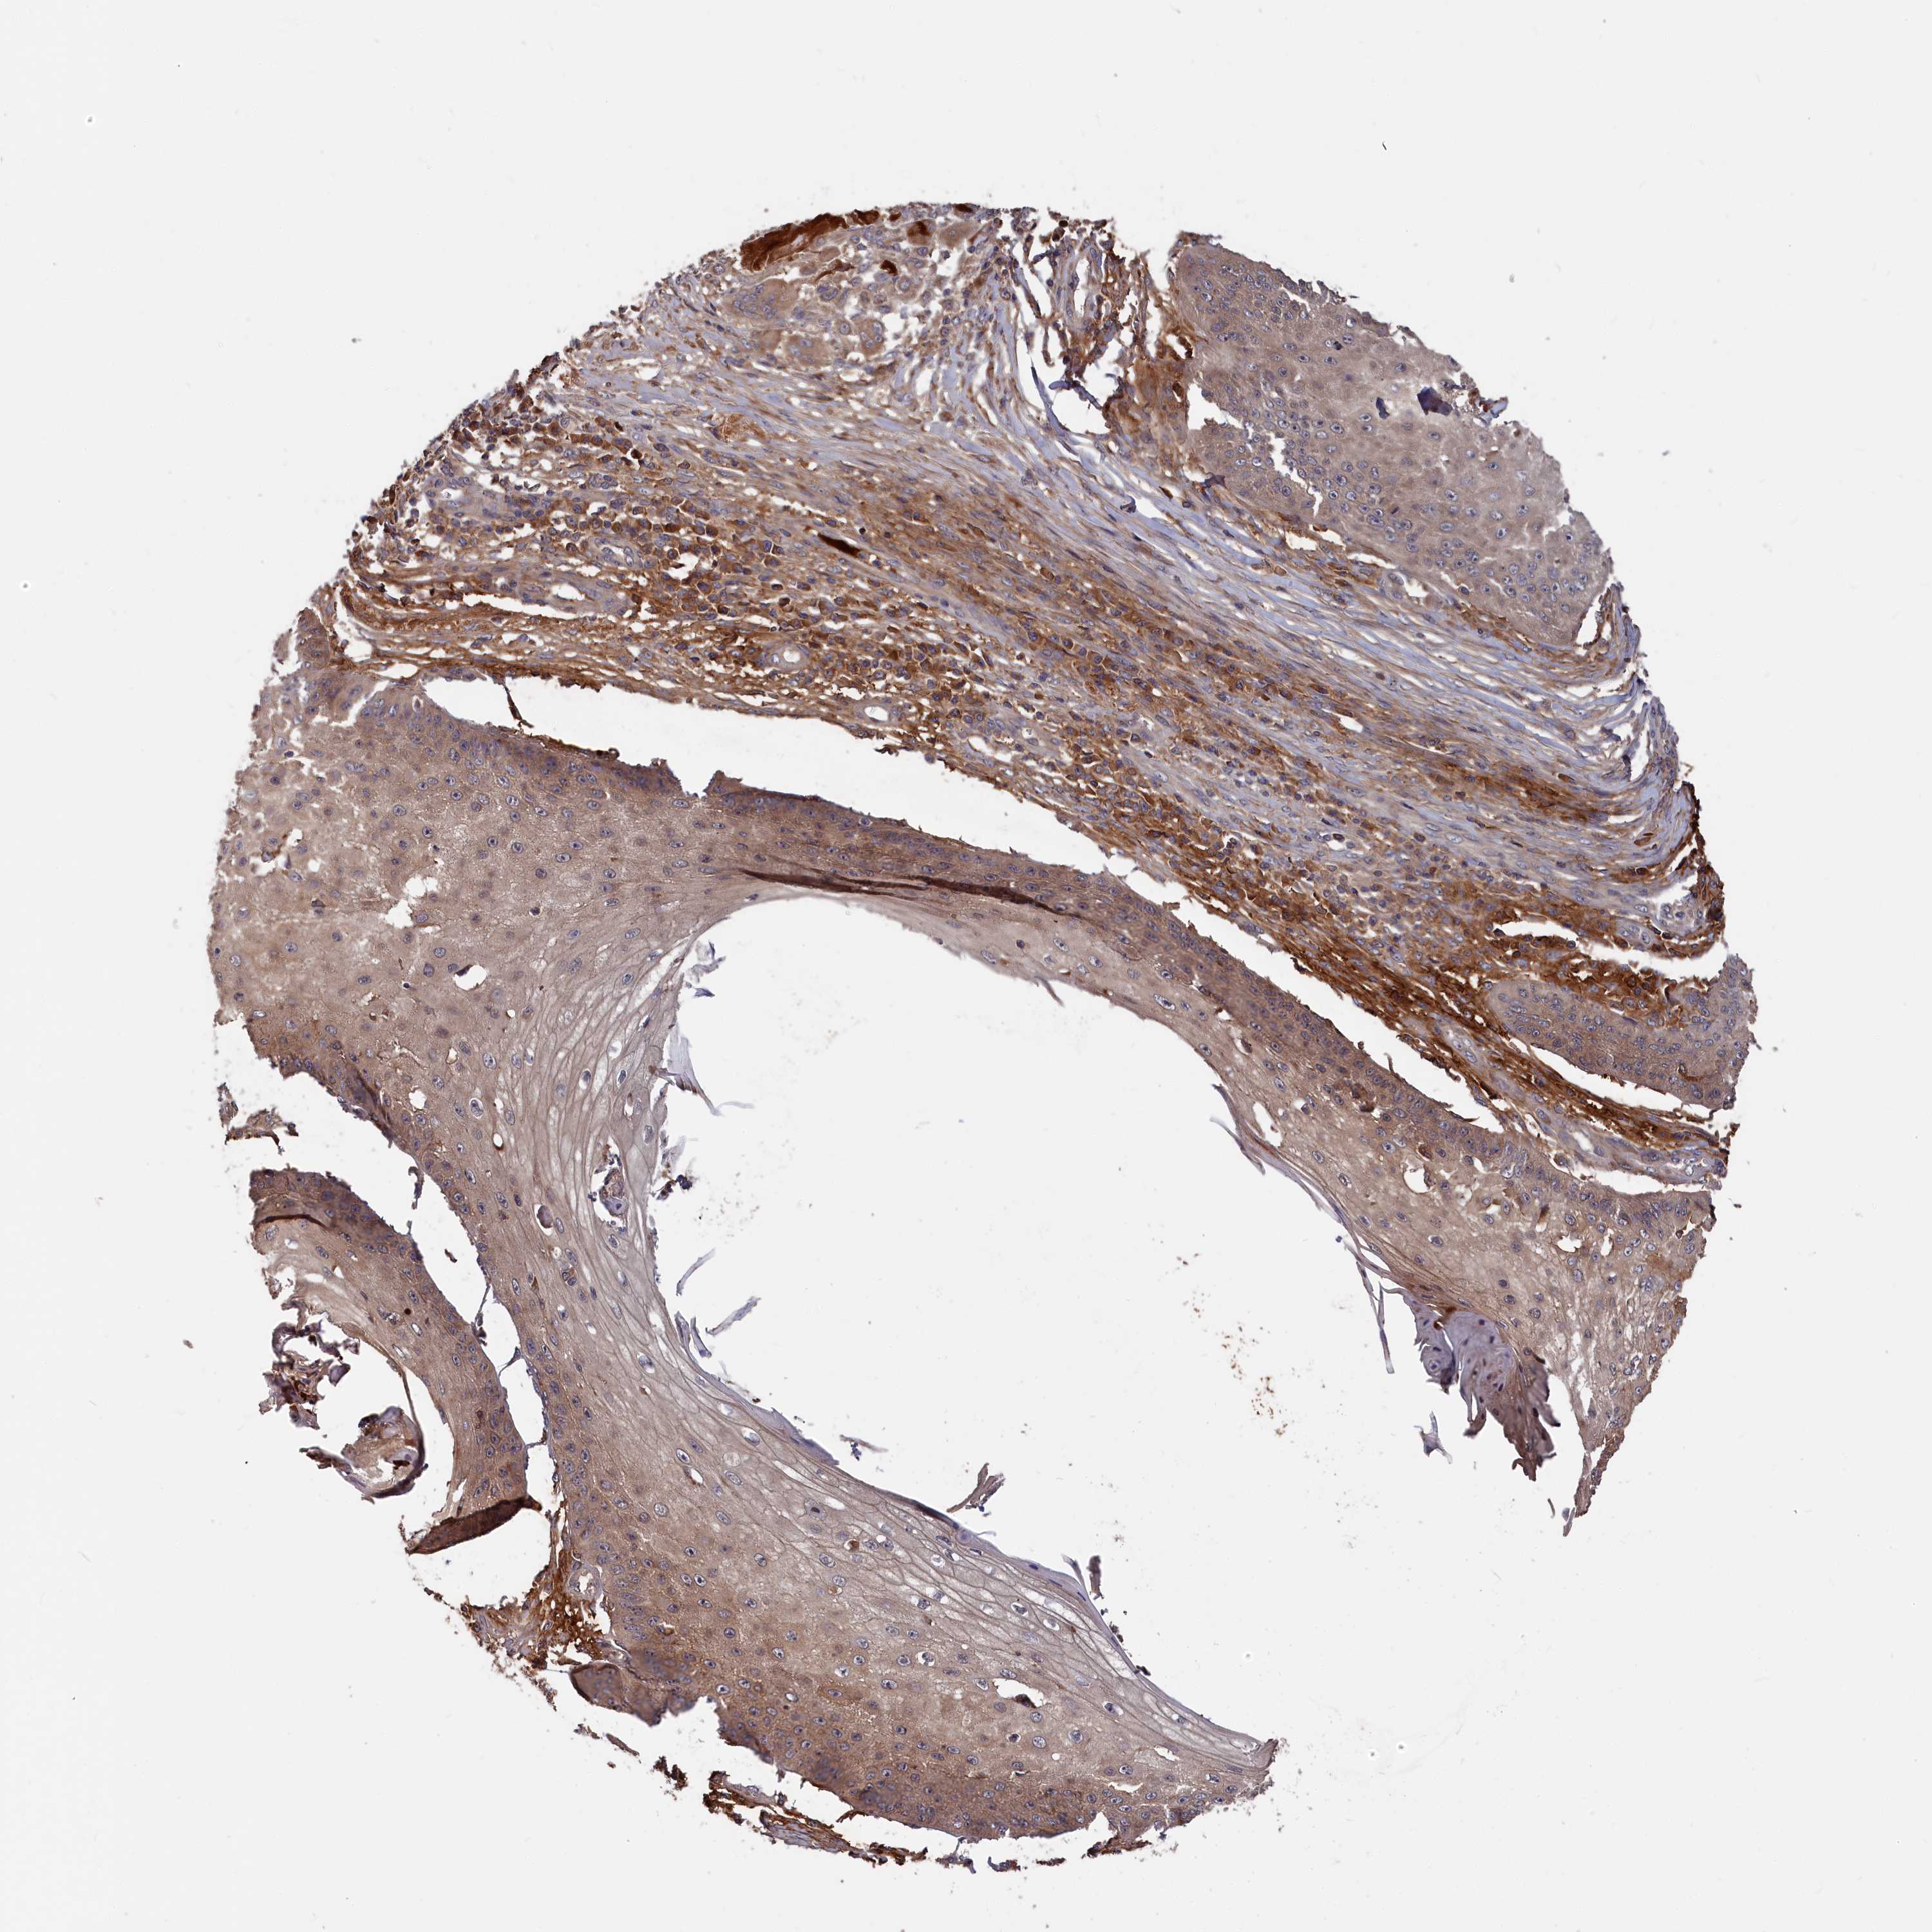

Basal cell and squamous cell cancer

SKIN CANCER - Protein expressioni

A mouse-over function shows sample information and annotation data. Click on an image to view it in a full screen mode. Samples can be filtered based on level of antibody staining by selecting one or several of the following categories: high, medium, low and not detected. The assay and annotation is described here.

Antibody stainingi

Antibody staining in the annotated cell types in the current human tissue is reported as not detected, low, medium, or high, based on conventional immunohistochemistry profiling in selected tissues. This score is based on the combination of the staining intensity and fraction of stained cells.

Each image is clickable and will lead to virtual microscopy that enables deeper exploration of all samples and also displays staining intensity scores, fraction scores and subcellular localization as well as patient and tissue information for each sample.

Antibody HPA041639

Antibody HPA042049

Staining

High

Medium

Low

Not detected

Intensity

Strong

Moderate

Weak

Negative

Quantity

>75%

75%-25%

<25%

None

Location

Nuclear

Cytoplasmic/membranous

Cytoplasmic/membranous,nuclear

Basal cell carcinoma

Squamous cell carcinoma, NOS

Squamous cell carcinoma, metastatic, NOS